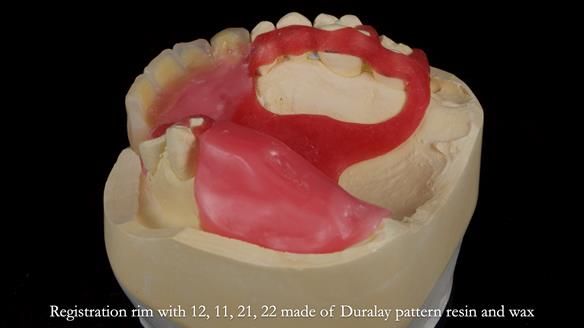

Keith’s combat denture case study

Keith’s case was one of the most challenging and rewarding cases I’ve treated this year. This 64 year old man presented with ill-fitting acrylic partial dentures that lacked stability, retention, and aesthetics. They constantly broke. He had lost the upper front teeth in a road traffic accident in his early 20s. The unopposed teeth had erupted, taking up space. After careful planning, we made a durable, metal-based upper partial denture/splint to address his dental concerns. He loved the outcome.

1. Denture design: A custom cobalt-chromium framework was Scandinavian-designed to maximise stability, protect the remaining teeth, and allow for future additions if needed.

Keith’s denture incorporated a Duracetal shell clasp on upper right first premolar (Myerson), which are designed to be virtually visible, providing a more aesthetic solution while enhancing patient comfort. The Scandinavian-inspired approach, based in modern removable prosthodontic techniques, ensured the denture was not only durable but also visually pleasing. Additionally, the design was carefully planned to allow for future modifications, ensuring that if Keith loses additional teeth, the denture can be adapted rather than replaced entirely.

I also used the Dahl concept to re-establish the occlusion upon fitting the RPD, which helped to intrude the lower left canine without needing to grind it too much.